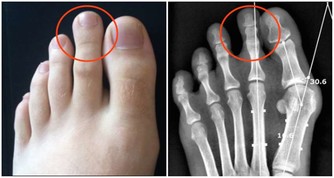

1、靜脈曲張和靜脈血栓患者

熱水泡腳時,下肢動脈擴張,尤其表現為皮膚充血,更多的動脈血液進入下肢。

然而,靜脈的回流能力並不會因此增加;於是,熱水泡腳對於本來回流不暢或阻塞的靜脈病患者來講,會加重血液淤積;此外熱水泡腳,還可以導致毛細血管破裂,形成皮膚上的出血點;時間久了,就會形成色素沉著,小腿顏色變黑。